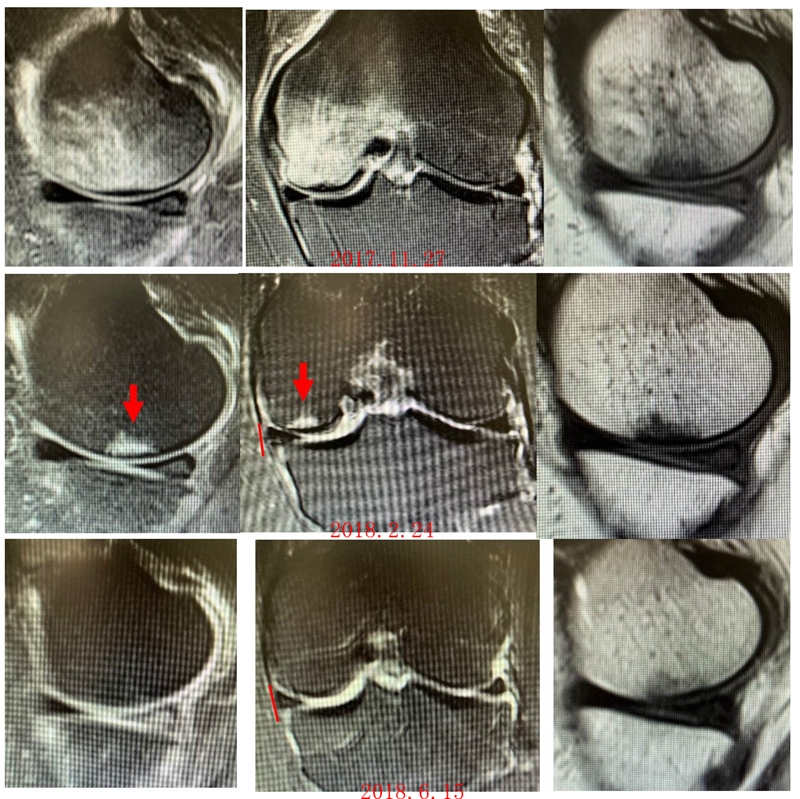

病例:女,65岁,主诉左膝关节内侧疼痛2月余。2017年11月X光未见左膝骨质异常。MR见股骨内侧髁骨坏死,半月板相对突出百分比(RPE)28.3%,合并内侧半月板后根部撕裂,矢状位病变区域前后径为11.67mm,关节线会聚角2.68°

予消炎止痛药物口服、静滴唑来膦酸钠注射液,避免负重6周,后改部分负重,12周后全负重。

2018年2月复查MR见骨髓水肿明显吸收,坏死灶边界清晰,半月板相对突出百分比(RPE)28.92%

2018年6月复查MR见骨髓水肿基本完全吸收,坏死区修复良好,半月板相对突出百分比(RPE)38.54%,患者临床症状消失。

提示坏死好转了,但半月板突出进展了,膝关节的退变加重了。